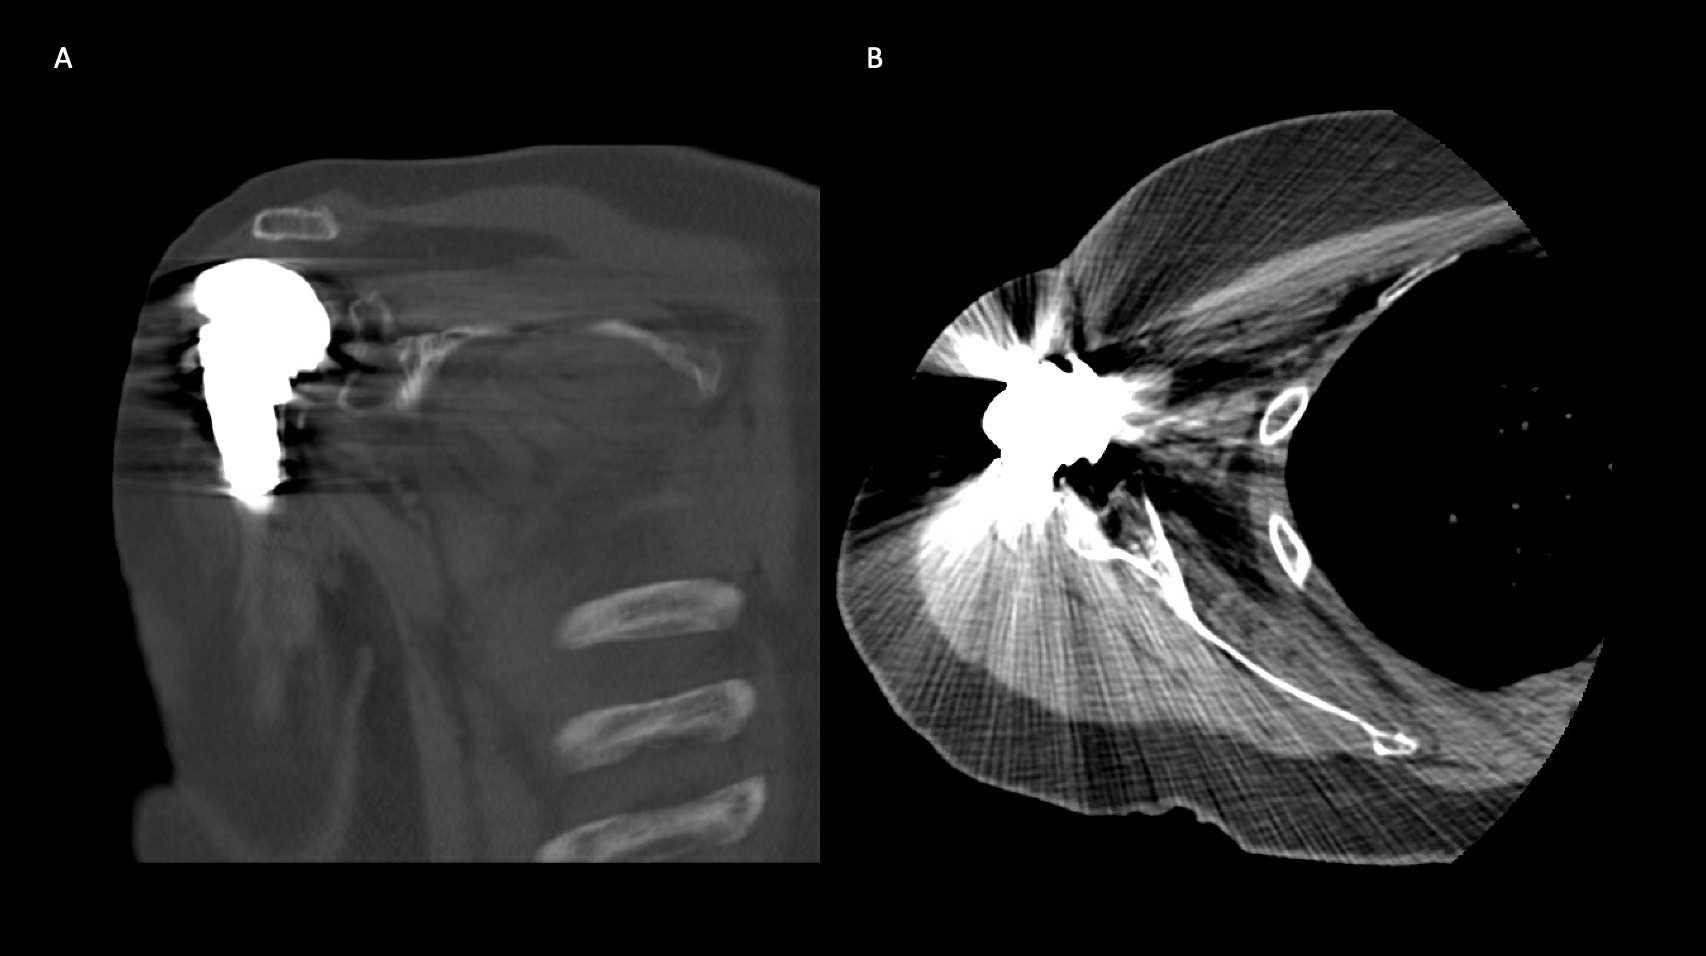

A 69-year-old woman presented after resection arthroplasty of her right shoulder hemiarthroplasty and completion of antibiotic treatment for culture negative PJI for evaluation of reconstructive options. She had a history of a displaced two-part right proximal humeral fracture which was repaired with an intramedullary nail. Post operatively, she had persistent pain and CT scan of the shoulder showed two screws in the humeral head that extended through the cortex and into the glenohumeral joint. The screws were removed and replaced with smaller screws. Subsequently, she had non-union of the fracture in the setting of deltoid weakness and was revised to a right hemiarthroplasty (Figures 1-3). Post operatively, she had persistent pain refractory to physical therapy and diminished function that was impacting her quality of life. She sought subsequent care, and there was concern for arthroplasty failure secondary to a septic versus aseptic condition and the decision to proceed with resection arthroplasty was made. During resection arthroplasty, a significant amount of fluid was expressed from the joint space. The combination of the clinical picture of progressive and persistent pain and the gross expression of fluid were concerning for PJI and the decision to treat was made. It was felt that the extent of humeral bone loss did not allow for a stable cement spacer, so none was placed. Intraoperative joint fluid cultures, anaerobic, and fungal cultures were all negative for growth. Cultures were held for 21 days to rule out C. Acnes infection. Considering the plan for future reimplantation, infectious disease consultation recommended a 6-week course of vancomycin but after 2 days the patient had a transfusion reaction and was switched to daptomycin. She was left with markedly limited active motion associated with severe pain. After completion of the antibiotic course, the patient elected to proceed with revision surgery. This patient had a flattened and distorted glenoid and atrophied rotator cuff musculature demonstrated prior to resection arthroplasty on CT (Figure 4). This patient’s prior hemiarthroplasty had been a tantalum coated, cemented humeral stem with associated marked thinning of the humeral cortex even prior to resection arthroplasty, and this resulted in a large amount of proximal humeral bone loss during the resection (Figure 5). The patient was severely debilitated by the right shoulder and wanted to proceed with reconstruction. Because of the combination of glenoid and humeral bone loss and the lack of rotator cuff attachments, a custom constrained prosthesis design process was initiated, and the implant was available 16 months after the resection arthroplasty. Preoperative 3 phase SPECT (Single Photon Emission Computed Tomography) three phase bone scan, upper extremity CT, and blood work (WBC 5.4, ESR 9, CRP 0.8) showed no suggestion of active infection.

A 62-year-old woman presented for evaluation of her reconstructive options after resection arthroplasty of a right rTSA and completion of antibiotic treatment for culture negative PJI. Her rTSA had been an Encore prosthesis placed due to rotator cuff arthropathy (Figures 6). Post-operatively she had persistent pain, stiffness, and tenderness to palpation that was treated with physical therapy, a steroid injection, and manipulation under anesthesia. An infectious work up due to the chronic and persistent nature of the pain showed WBC 7.4, ESR 53, CRP 1.2. Patient denied further work up with a tagged white cell scan and preferred continued clinical monitoring to observe pattern of symptoms. Eleven months later, she endorsed persistent pain. Repeat infectious work up showed WBC 4.5, ESR 13, and CRP 1.1. Despite the normal inflammatory markers, a 10-day trial of Augmentin was initiated and failed to change her symptoms. The decision to proceed with 1 vs 2 stage reconstruction was made. During resection arthroplasty, a substantial amount of fluid was expressed from the joint capsule concerning for PJI. A cement spacer was placed, and the patient was treated with 6 weeks of vancomycin and cefepime (Figure 7). There was proximal humeral bone loss as the result of resection arthroplasty due to the humeral stem. The glenoid component was loose and associated with glenoid bone loss, further complicated by the need for removal of a broken central screw (Figure 8).

Intra-operative frozen sections, tissue cultures, and gram stain showed no signs of infection. Following treatment, inflammatory markers remained normal (WBC 5.5, ESR 22, CRP 0.9), and aspiration of the shoulder showed no organisms on gram stain and no growth on aerobic, anaerobic, fungal, and acid-fast bacilli cultures. Cultures were held for 21 days to rule out C. Acnes infection. She was left with profoundly limited active motion and severe pain and the patient elected to proceed with revision surgery. Because of the combination of severe glenoid and humeral bone loss and the lack of rotator cuff attachments necessitating a design with additional constraint, the decision to proceed with custom prosthesis design was made 9 weeks after resection arthroplasty.